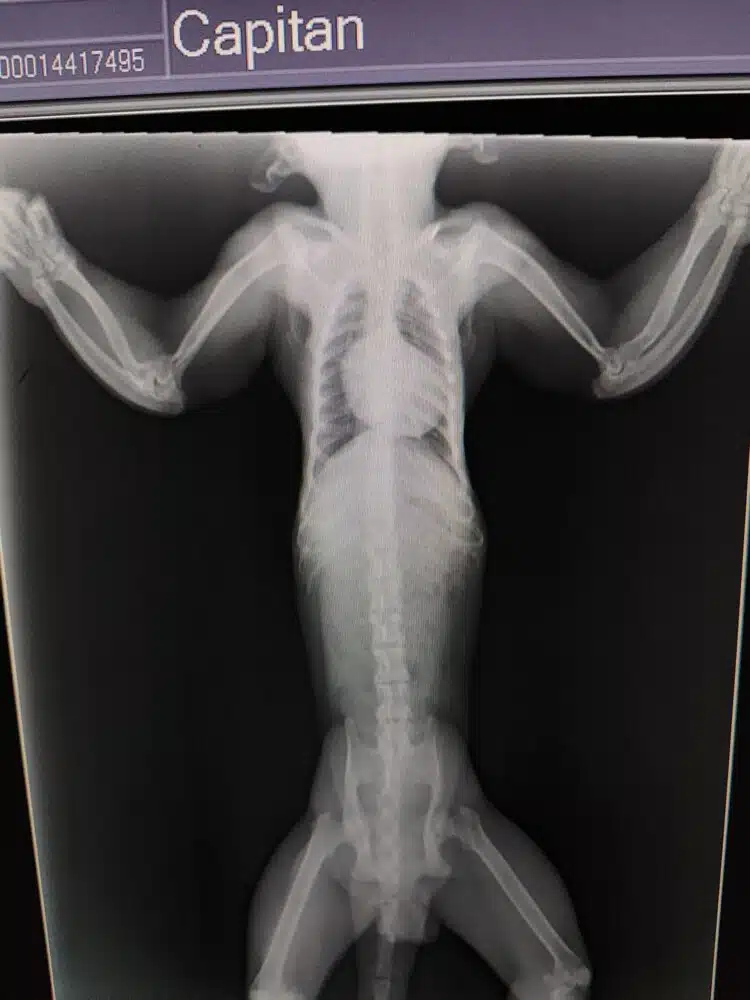

Bovendien laten röntgenfoto’s tekenen van een stofwisselingsziekte van de botten zien. Deze aandoening wordt veroorzaakt door slechte voeding en een gebrek aan blootstelling aan zonlicht, wat nodig is voor de aanmaak van vitamine D. Vitamine D speelt een belangrijke rol bij de opname van calcium en de vorming en dichtheid van botten.Als de botstofwisseling is verstoord, kunnen botten zich niet goed ontwikkelen. Hierdoor worden ze broos en groeien ze krom.

Bij Capitán zijn de ellepijp en het spaakbeen (onderarmbotten) misvormd. Daarnaast lijkt hij een oude breuk in zijn linkeronderarm te hebben. Deze misvormingen zijn te verklaren door lage botdichtheid. Ook in zijn beide bovenarmen zijn de botten slecht ontwikkeld.

Tijdens het veterinaire onderzoek konden de armen van Capitán niet volledig worden gestrekt. Uit röntgenfoto’s bleek dat hij ook artrose en vergroeiingen in zijn ellebogen heeft.

Deze gewrichtsslijtage en gedeeltelijke vergroeiing van de elleboogbotten kunnen ook veroorzaakt zijn door de stofwisselingsziekte van de botten.